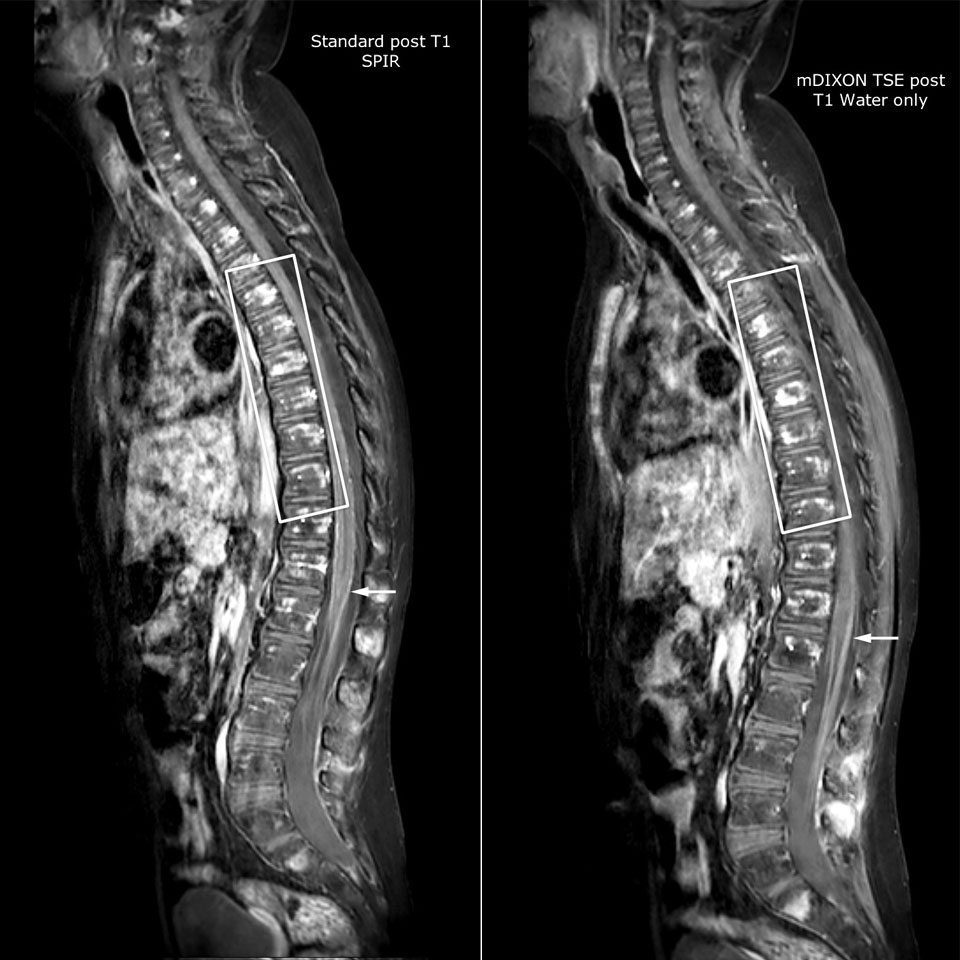

Philips mDIXON TSE is a two-point DIXON technique that separates water and fat signals, for time-efficient fat-free imaging, even in challenging neuro anatomy.

“mDIXON TSE has been one of the most significant improvements in imaging sequences that we have utilized to date at PCH,” says Dr. Miller. “Its multi-parametric acquisition allows us to obtain fat suppressed images and equivalent non-fat suppressed T2 images all in the same sequence. In addition, prior methods of fat suppression could be artifactually corrupted by poor patient anatomy or poor operator application, but with mDIXON we now have a robust and reliable method of fat suppression.”

Fat saturation is historically challenging at the ends of fields of view, especially in total spine imaging and in difficult patient anatomy such as the lower regions of the neck. “Due to the unique fat suppression capabilities of mDIXON, however, these challenges no long apply,” says Dr. Miller. “We routinely obtain homogeneous fat suppression under virtually all conditions. It has also led to some efficiencies by not having to repeat sequences because of that technical failure.”

mDIXON TSE makes a difference

“mDIXON TSE is most useful in patients with lesions or abnormalities in the soft tissues such as the face and neck, and for patients with contrast enhancing abnormalities that are mostly visible with fat suppression,” says Dr. Miller. “All our spine imaging now routinely contains mDIXON water-only T2 images, and this allows us to identify pathology that may be obscured by non-fat suppressed imaging such as injuries of the bone. And it’s not necessary to obtain additional standard TSE T2 images because the in-phase mDIXON images are equivalent to standard TSE T2 images.”

“mDIXON TSE has increased our diagnostic confidence in ruling in or ruling out abnormalities in which fat suppression is critical to diagnosis, such as metastatic disease or osseous abnormalities.”

Miller JH, Pokorney A, Naidu P, Eggers H, Shar M, Perkins T. Improved Fat Suppression and Field Homogeneity of mDixon TSE Total Spine Imaging compared to SPIR Fat Saturation for Post-Contrast T1-weighted Imaging. Proceedings of the Joint Annual Meeting of the ISMRM-ESMRB. Milan, Italy: International Society for Magnetic Resonance in Medicine, 2014.